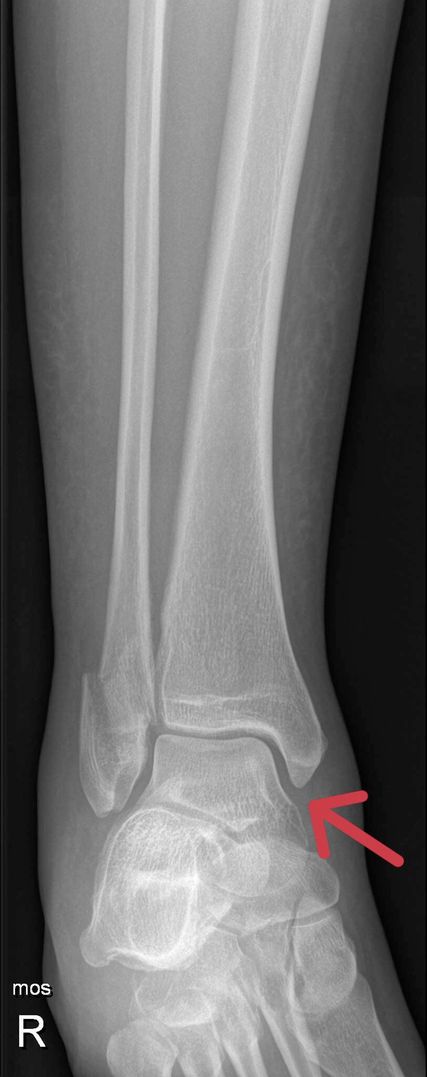

Als Standarddiagnostik erfolgt eine Röntgenaufnahme des Sprunggelenkes in zwei Ebenen. Die a.p-Aufnahme wird in 15–20° Innenrotation des Unterschenkels (Mortise-View) durchgeführt. Zur Beurteilung der Integrität des Deltabandes ist der Abstand zwischen Sprungbein und der lateralen Kortikalis des Innenknöchels („medial clear space“, MCS), entscheidend. Bei Werten <4mm ist das Deltaband intakt und die Fraktur stabil. Ist der MCS größer als 4mm oder gibt es klinische Zeichen einer Deltabandverletzung, muss weitere Diagnostik zur Feststellung der Stabilität durchgeführt werden.

Eine weitere Möglichkeit ist die Röntgenaufnahme im Stehen unter Vollbelastung nach 5–10 Tagen. Zeigt sich hierbei ein unauffälliger MCS, werden in der Literatur gute klinische Ergebnisse bei konservativer Behandlung beschrieben. Dawe et. al stellten fest, dass der „Gravity-Stresstest“ bei Außenknöchelfrakturen signifikant häufiger positiv ausfällt als der Röntgenbelastungstest (45% vs. 3,7%). Dementsprechend höher war die Anzahl der operierten Patienten und der damit verbundenen Komplikationen. In der Studie von Holmes et. al wurden bei 51 Patienten mit einem MCS <7mm (∅ 4,42mm) im „Gravity-Stresstest“ normale Werte in der Röntgenuntersuchung in Vollbelastung beobachtet. Diese Patienten wurden konservativ behandelt und zeigten gute klinische und radiologische Resultate. 90–98% der isolierten Außenknöchelfrakturen können trotz positiver „Stresstests“ oder klinischer Zeichen einer Instabilität bei negativem Röntgenbelastungstest konservativ mit gutem Outcome behandelt werden.